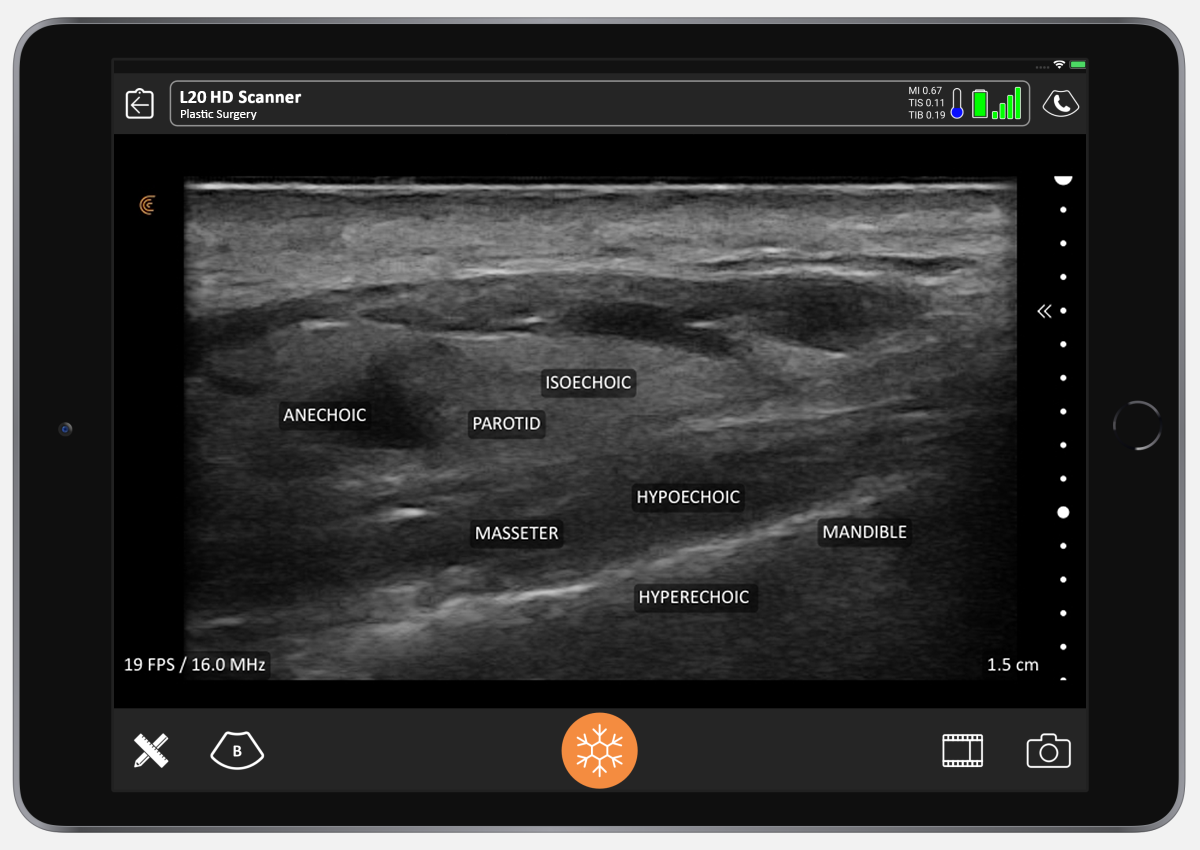

Interest in doppler ultrasound (dus) analysis of the face has grown in cosmetic medicine, in particular for injectable fillers. The article reviews the types, properties,. In the context of filler application, live visualization with ultrasound can be utilized pre and postprocedurally to evaluate critical.

UltrasoundGuided Techniques to Rapidly Dissolve Fillers, Part 1 Misplaced Facial Fillers Clarius Face Filler Ultrasound Interest in doppler ultrasound (dus) analysis of the face has grown in cosmetic medicine, in particular for injectable fillers. The article reviews the types, properties,. In the context of filler application, live visualization with ultrasound can be utilized pre and postprocedurally to evaluate critical. Face Filler Ultrasound.